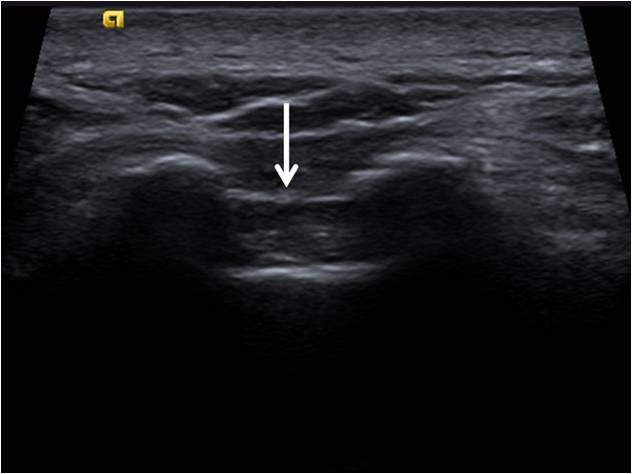

Le hiatus sacré (ou échancrure sacrée ou hiatus sacro-coccygien) est une échancrure formée par la divergence des cornes du sacrum à l’extrémité inférieure de la crête sacrale médiane.

Il est situé au niveau des deux dernières vertèbres sacrées et limite l'orifice inférieur du canal sacral.